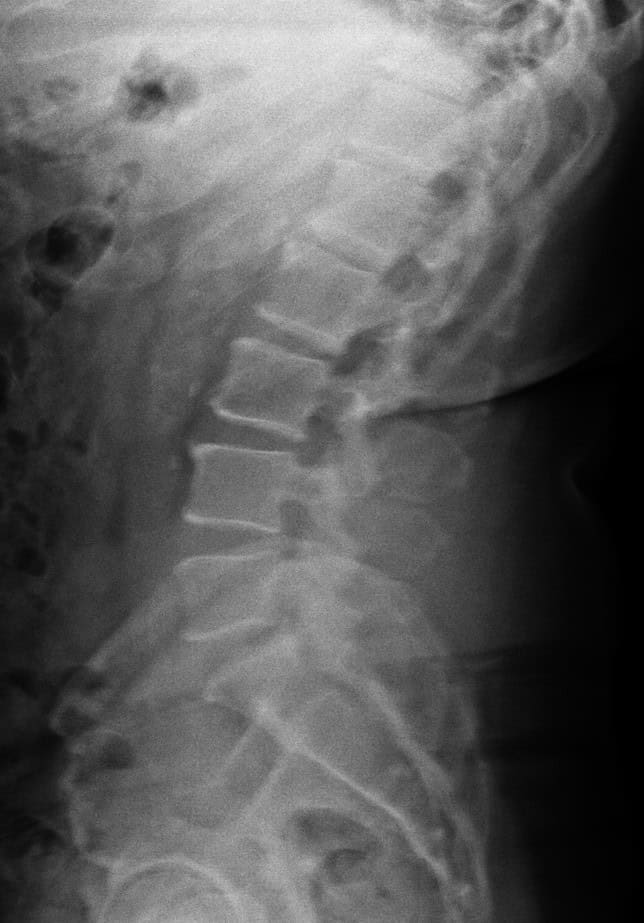

Ed’s journey with us began in 2016, just four months after experiencing a stroke that left him with significant challenges. One of the most noticeable effects of the stroke was that it caused him to drag his right leg, making walking difficult and uncomfortable. On top of that, he was struggling with severe sciatica pain, which made simple activities like walking or sitting extremely uncomfortable and limited his independence.

When Ed came to us, he was seeking relief and support to help him regain mobility, reduce pain, and improve his overall quality of life. Through consistent care and a tailored program designed to address his nervous system and musculoskeletal needs, Ed has experienced meaningful improvements over time.